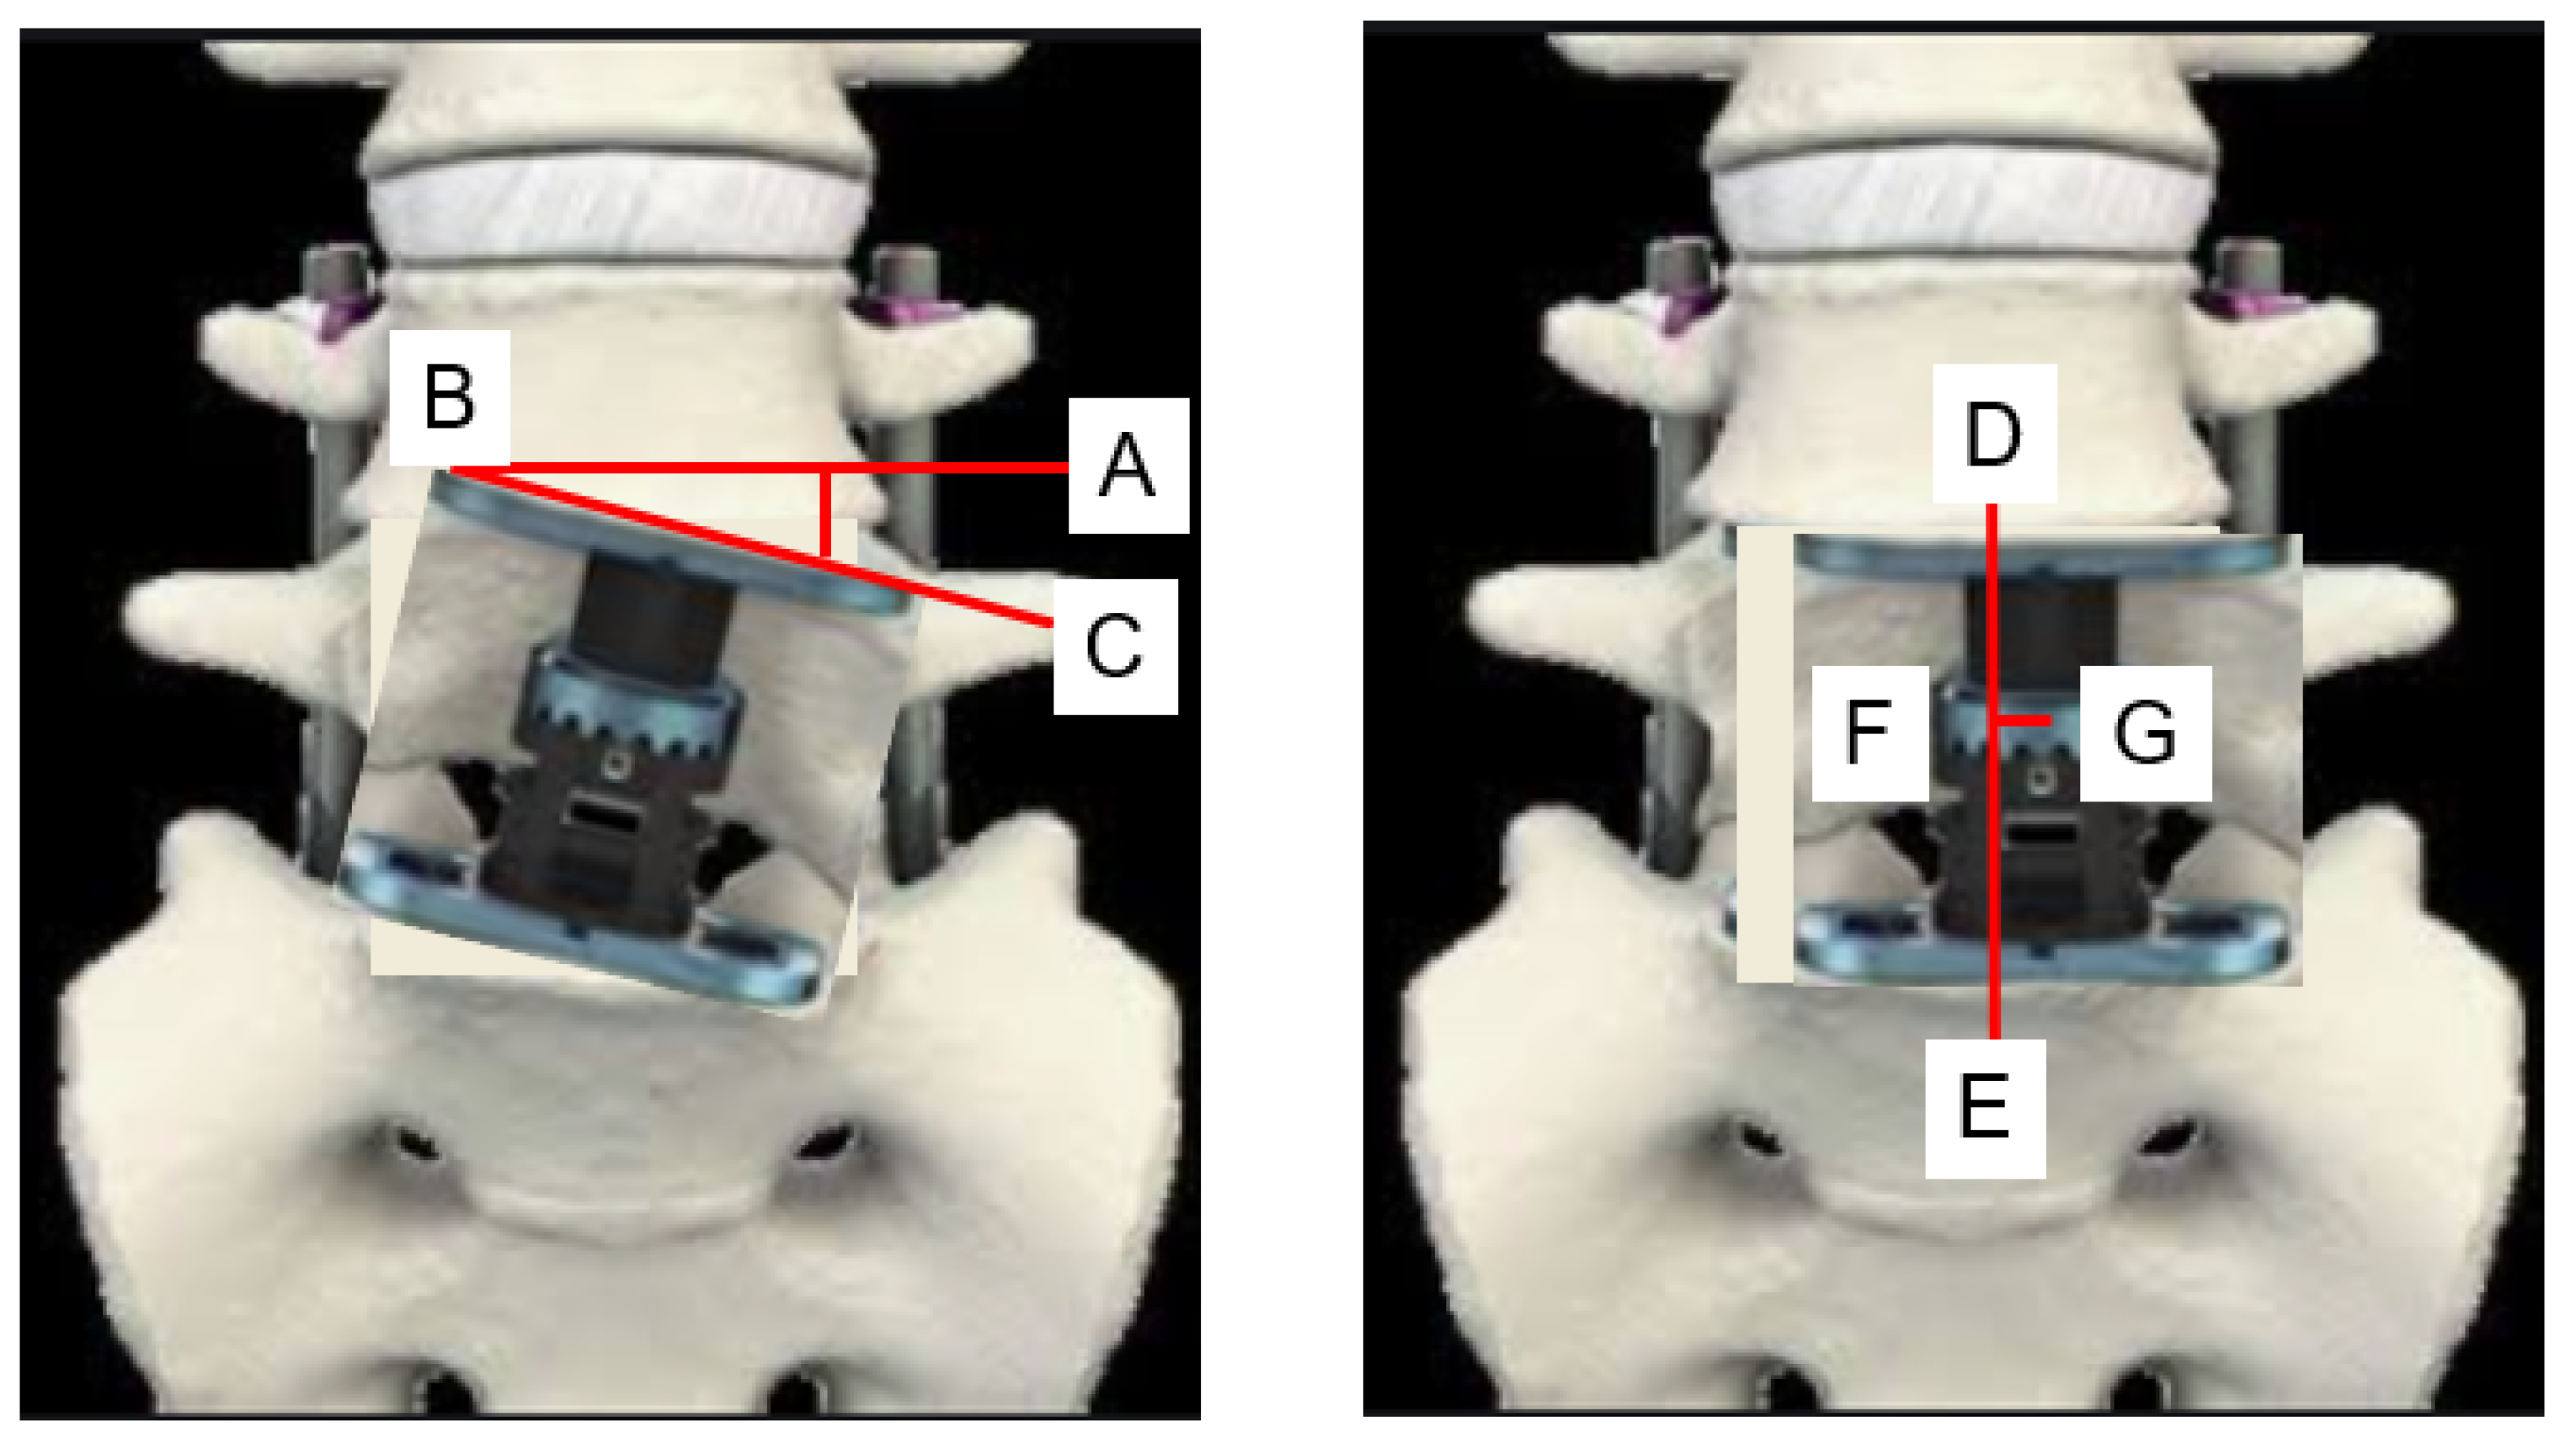

2.3. Radiographic Evaluation

3.2. Radiographic Evaluation